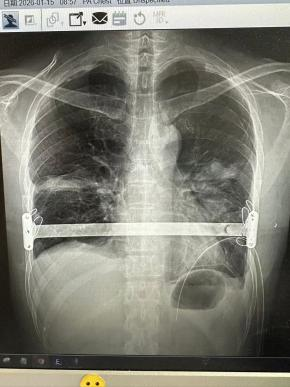

Patient: A 37-year-old man.

Challenge: Years earlier, he had undergone pectus surgery at another institution that failed to correct the deformity, leaving him with ongoing pain and disappointment. Revision surgery is notably more complex due to existing scar tissue and altered anatomy.

Solution: Dr. Li Guoqing carefully analyzed the previous surgery and developed a new plan. He performed a revision procedure, skillfully navigating scarred tissue to place a single, strategically positioned bar.

Outcome: The surgery was a complete success, finally delivering the correction the patient had long sought. This case underscores that excellent results are possible even after prior unsuccessful surgery—when performed by an experienced specialist.